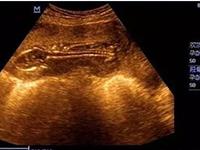

试管婴儿母亲是指采用试管受精技术而怀孕的母亲。试管受精是一种复杂的医疗程序,有一定的医学风险。母亲可能会遭受药物的不适反应和手术风险。对于接受试管婴儿技术的母亲来说,有可能出现后遗症。